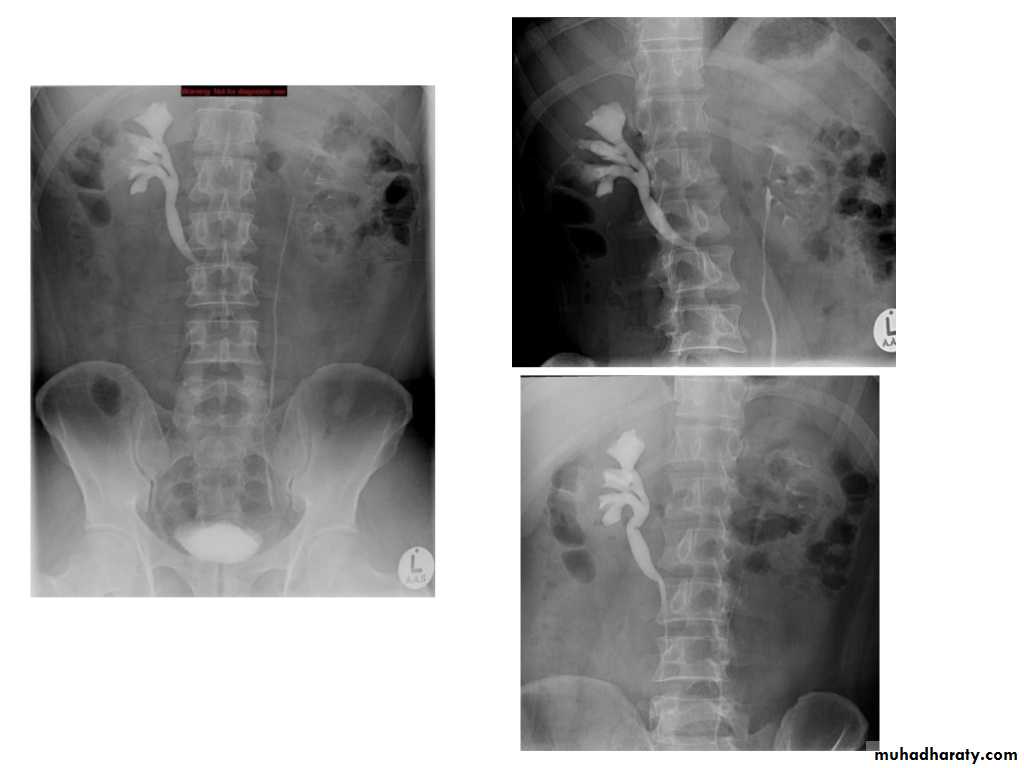

IVU shows

1. The kidneys at low position .2.Close to the spine with long axis parallel to the spine

3. Malrotation manifested by medially directed calyces.

4- The renal pelvis and ureters are anterior and lateral in position.

5- Hydronephrosis and calculi highly associated.